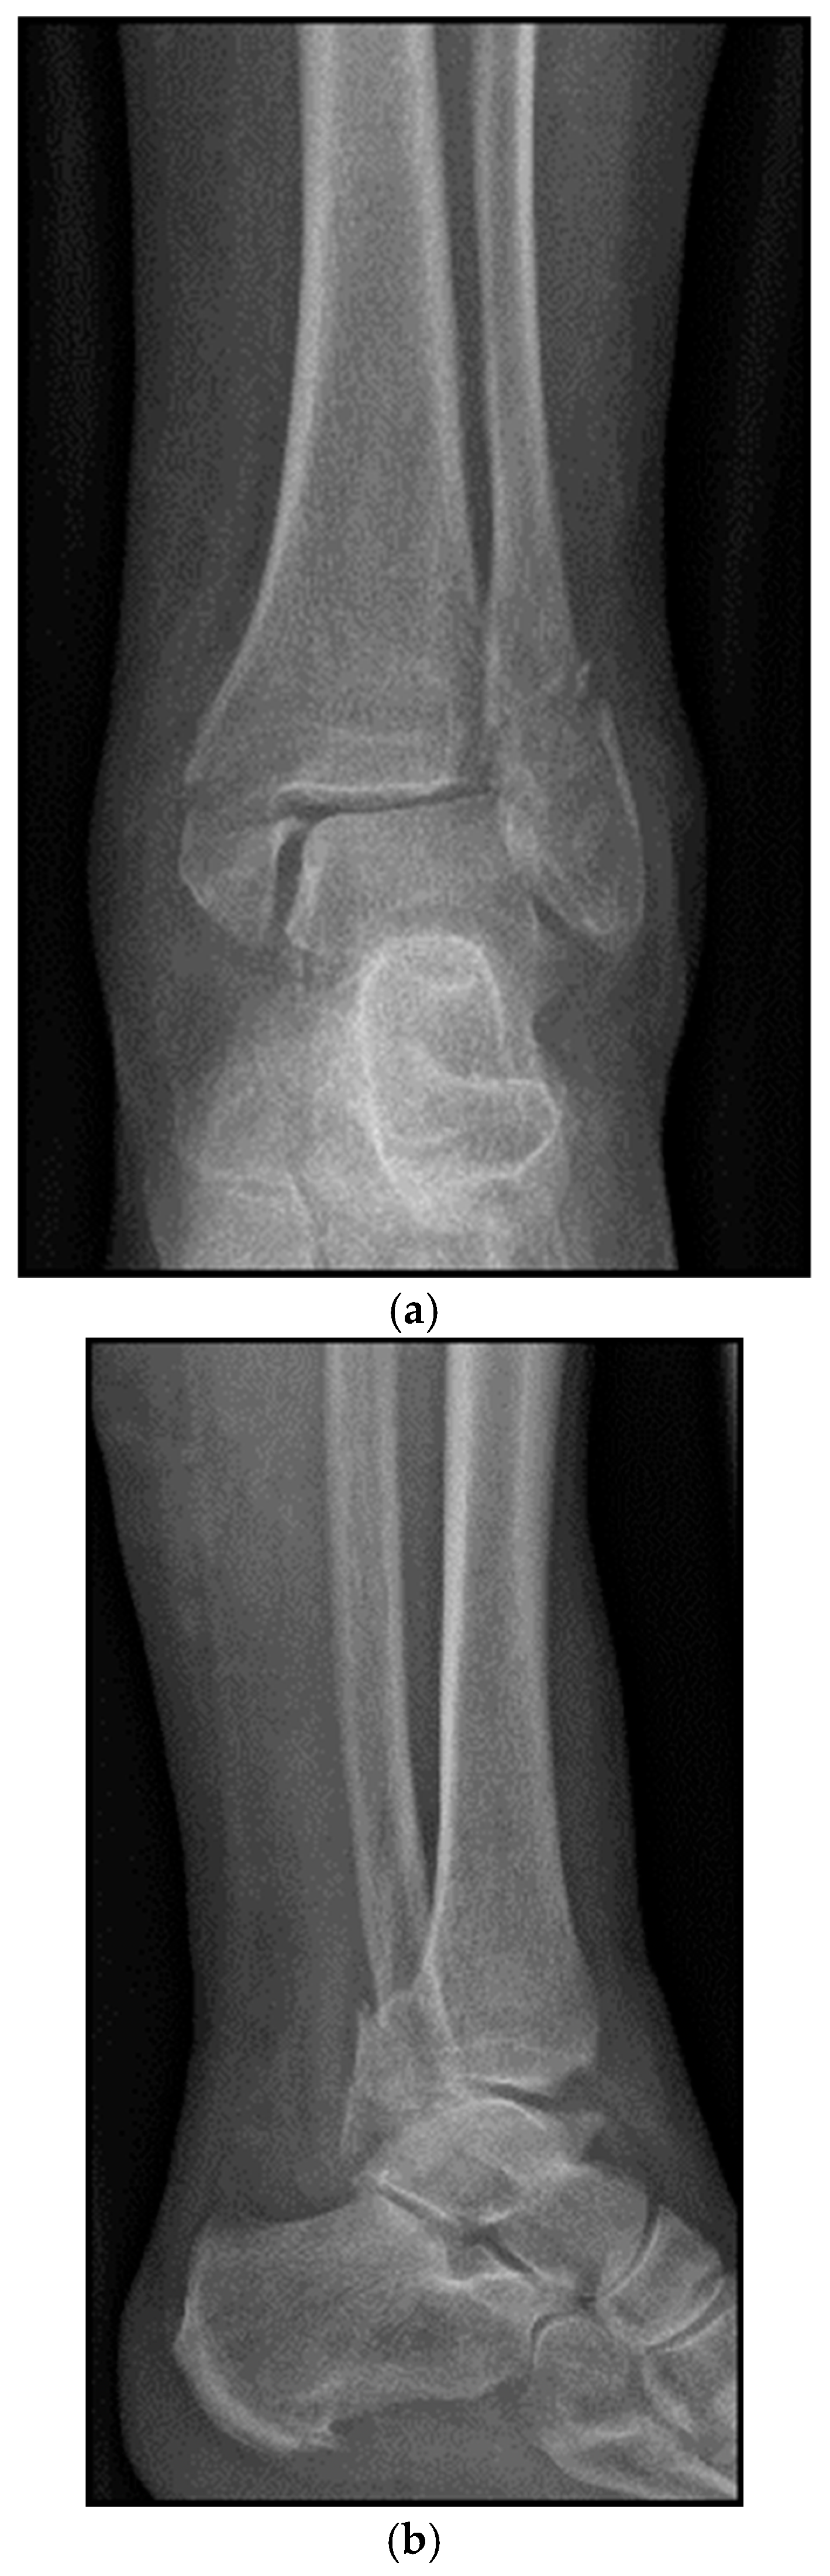

4. Classification

5. Case Description

5.1. Surgical Considerations